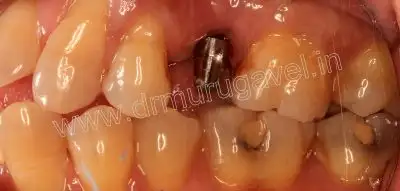

After implant placement

Day-2

- PMMA crown of proper contour and shade is fixed

- Advised patient to start eating food on that side..

- Patient was asked to report after 3 months for permanent crown

PMMA crown

post-op upper occlusal view

post-op side view